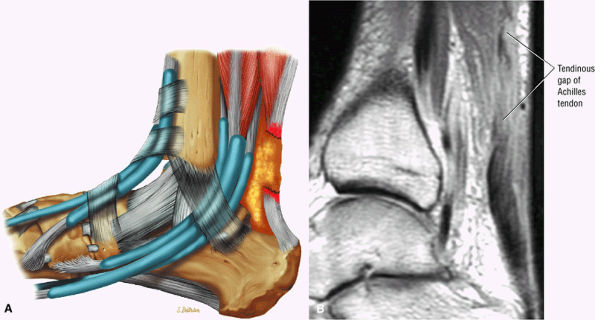

FIGURE 5.125 ● Type 3 or complete rupture of the Achilles tendon with a tendinous gap of 3 to 6 cm. (A) Lateral color graphic. (B) Sagittal PD FSE image.

Type 2: Complete ruptures with a tendinous gap of 3 cm or less (Fig. 5.124)

Type 3: Complete ruptures with a tendinous gap of 3 to 6 cm (Fig. 5.125)

A fluid-filled gap with or without interposed fat at the tear site in complete tendinous disruptions with discontinuity

Tendon disruption with discontinuity and a wavy retracted tendon

Complete tears demonstrate a hyperintense fluid-filled tendinous gap.

Tendon rupture usually occurs 2 to 6 cm superior to the os calcis.

The size of the rupture varies, based on the degree of tendon retraction.

Ruptures demonstrate diffuse convexity of the anterior margin and enlarged tendon ends at the tear site.